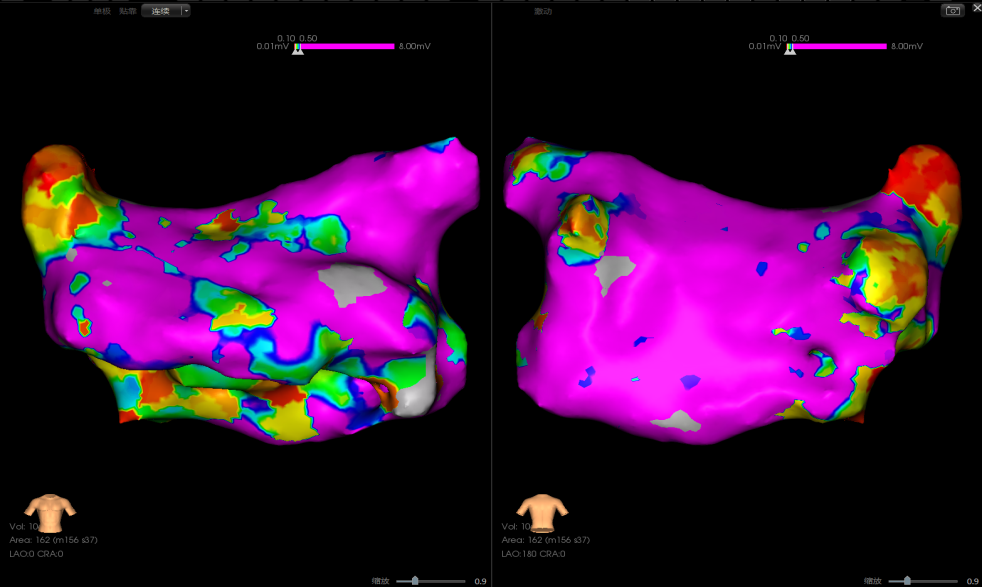

使用环形导管建模标测,患者后壁基质较好,前壁基质存在低电压区,左上肺静脉肌袖较深。

术中左侧和右侧肺静脉电位

消融后左/右侧肺静脉电位

PVI后房扑:肺静脉隔离后,房扑仍在发作且持续稳定,CS90早,周长220-230ms,遂进行激动标测。

激动图显示为绕着前壁瘢痕区的折返,后壁为被动传导。